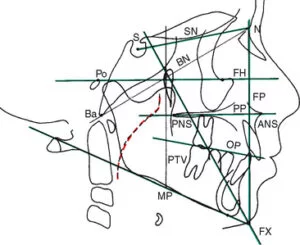

Cephalometric x-ray images are most commonly needed for orthodontic treatment. However, they can also be used for TMJ assessment, sinus evaluation and trauma to the jaw or skull. A cephalometric scan captures both lateral and poster-anterior (PA) images of the entire skull, and these scans are most commonly used as part of orthodontic treatment to measure relative movement of anatomical landmarks.

A somewhat unique characteristic that many dental professionals look for in their cephalometric images is the ability to see soft tissue. Specifically, they use the image to review the relationship a patient’s jaws and teeth have to their soft tissues and the entirety of their skull.

While the enhanced imaging of a direct conversion sensor has an impact with pan-only x-ray machines, it can be more pivotal for a ceph x-ray machine, because soft tissue landmarks are so important for orthodontic applications of cephalometric images.